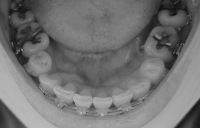

下から。

2008/4/15撮影

2008/5/20撮影

残る隙間は左側が1ミリ、右側が0.5ミリほど。